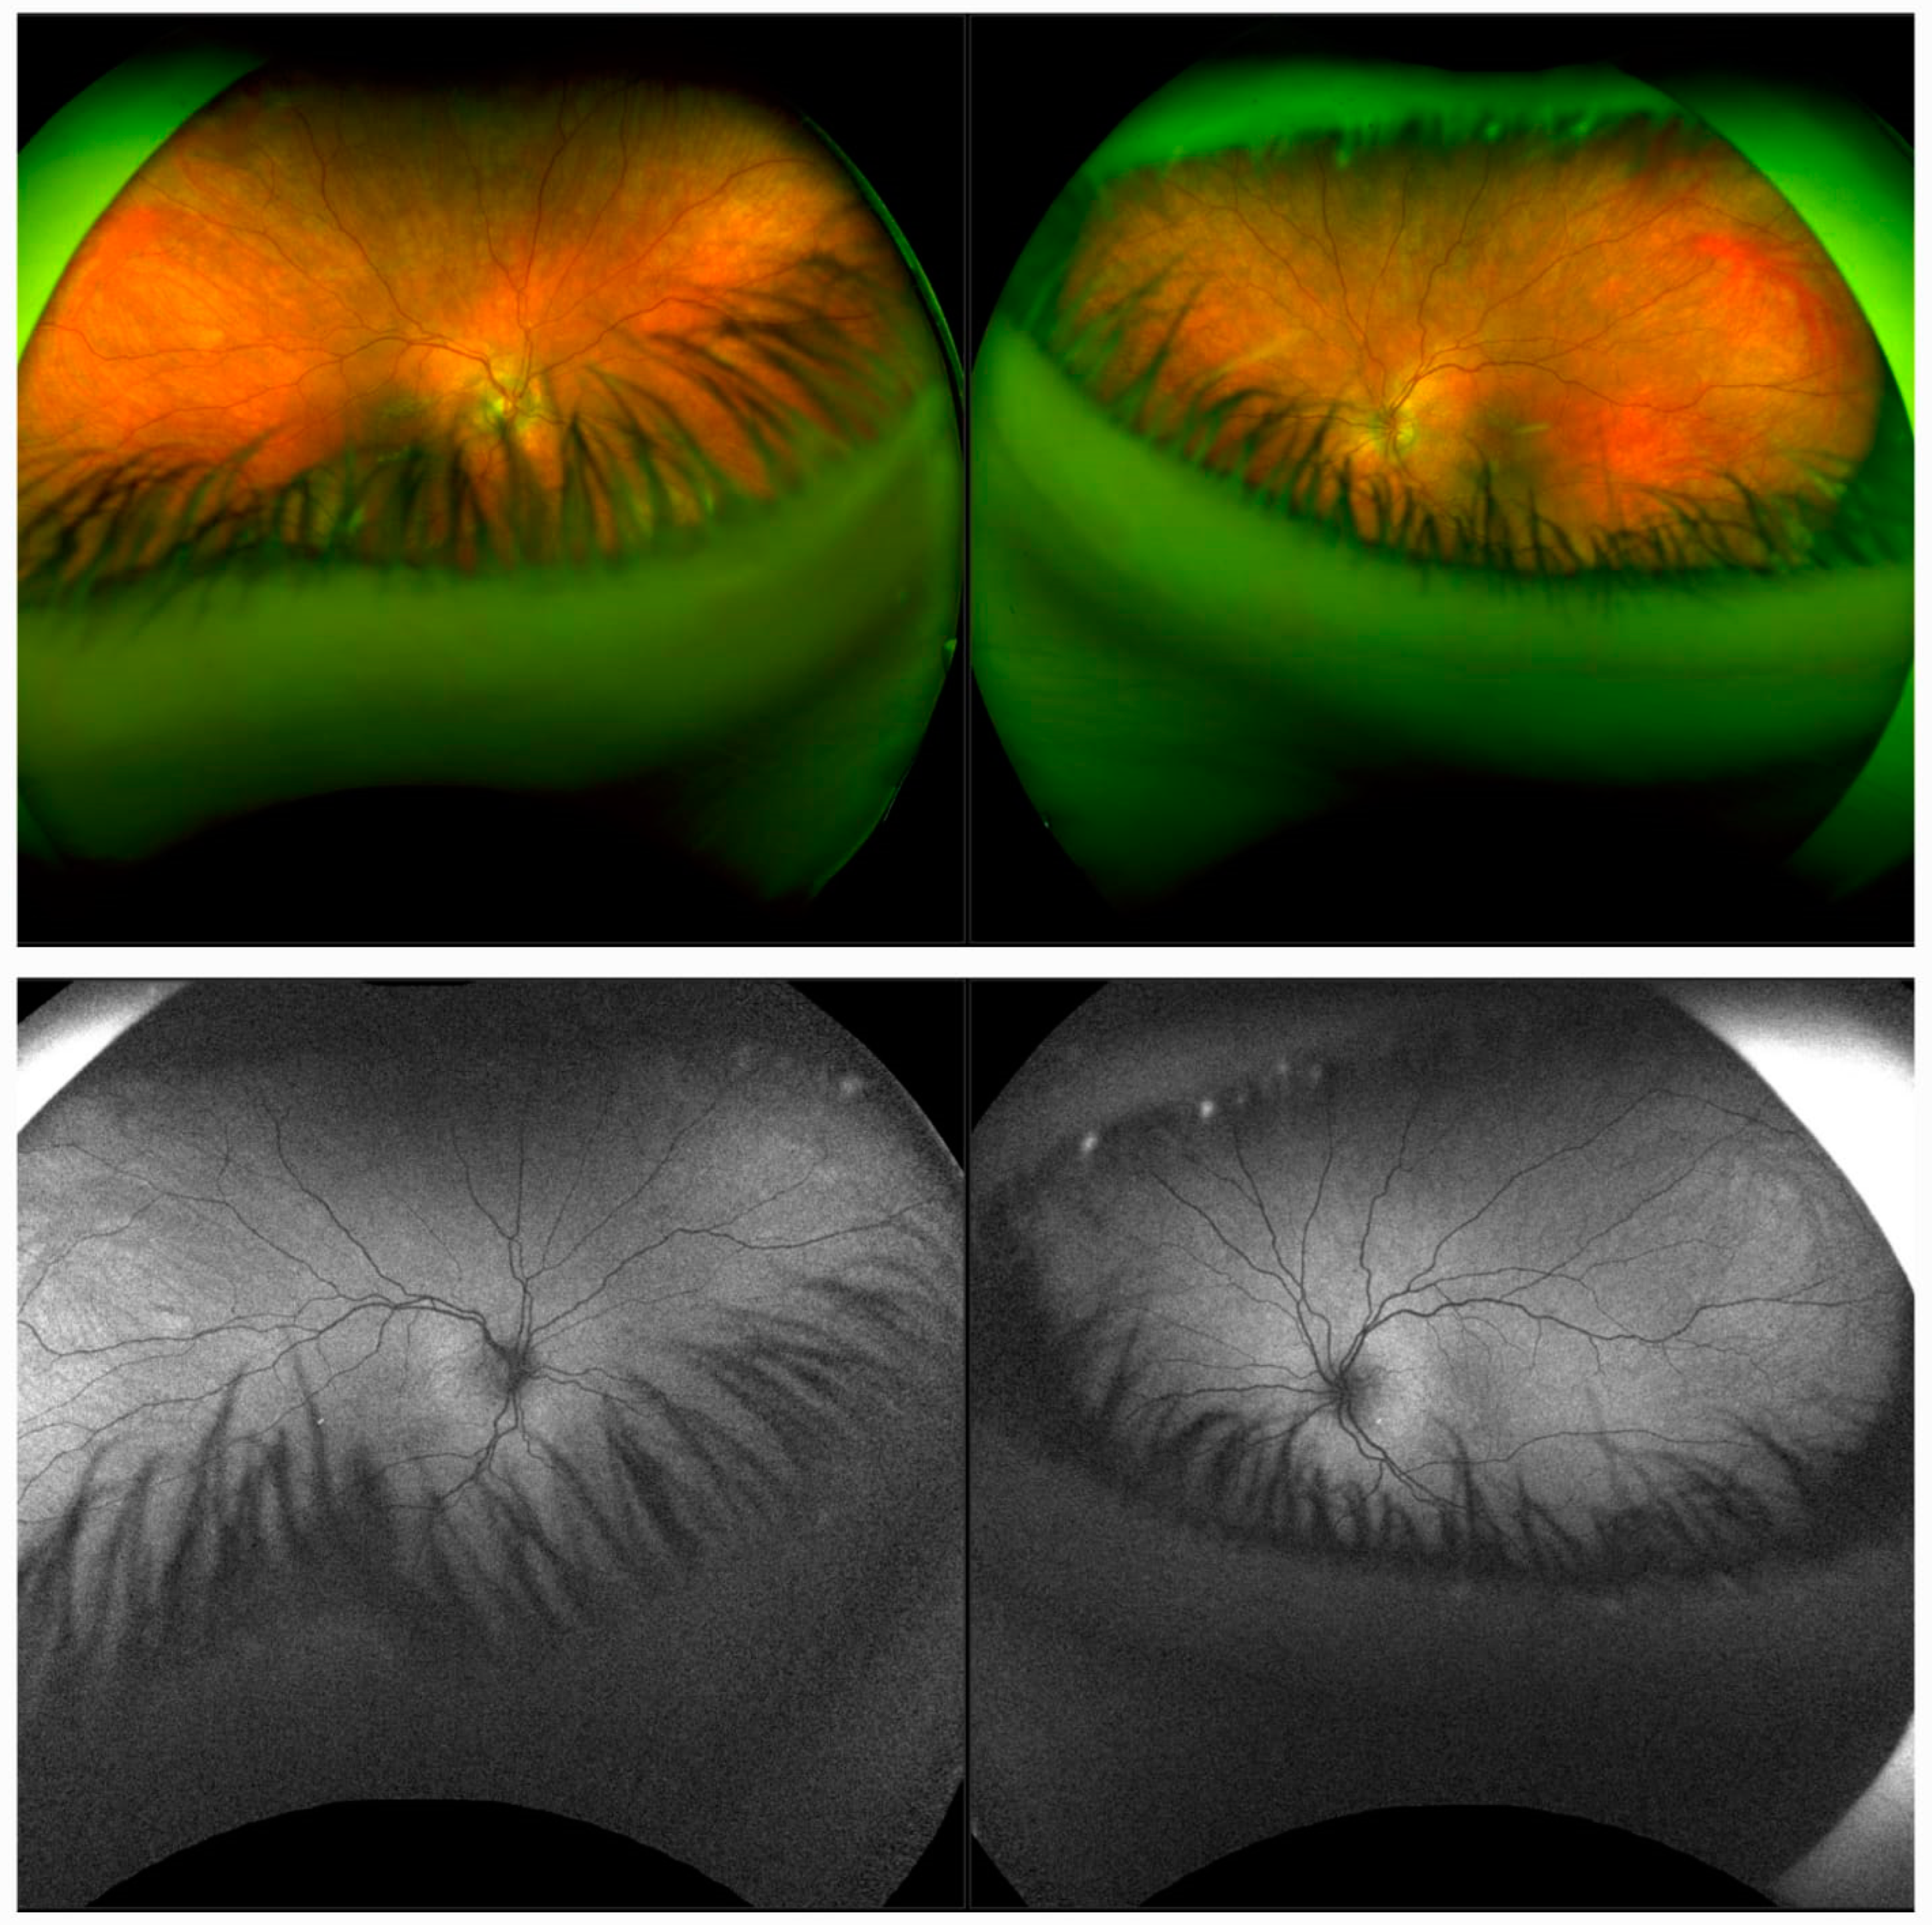

2.1. Case 1

2.2. Case 2